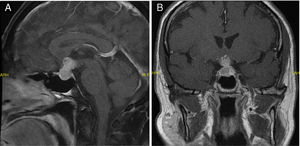

Caso 1: varón de 69 años, sin antecedentes de interés, derivado a endocrinología por sospecha de hipotiroidismo secundario con disminución de la TSH (0,15mUI/l) y la T4 libre (0,4ng/dl). Refería clínica de un mes de evolución de cansancio y somnolencia, xerosis, polidipsia y poliuria. Al ampliar la analítica se confirmó el hipotiroidismo secundario, y se detectó disminución de testosterona (0,03ng/ml) y cortisol (2,3μg/dl), y aumento de la diuresis (7.000ml/día) con osmolalidad urinaria baja (124mOsm/kg), diagnosticándose de insuficiencia suprarrenal, hipogonadismo hipogonadotropo y diabetes insípida. Se inició tratamiento sustitutivo con hidrocortisona, levotiroxina y desmopresina, con gran mejoría clínica y recuperación del peso. La RMN mostró una tumoración hipofisaria de 24×13×14mm con captación heterogénea del contraste (fig. 1A), y la campimetría fue normal. Se derivó a neurocirugía para resección. Para planificar mejor la intervención se repitió la RMN al ingreso, y se constató un aumento considerable de la tumoración hipofisaria en un mes, con diámetros de 32×35×32mm, que comprimía el quiasma óptico. La campimetría mostró una hemianopsia bitemporal. Tras la cirugía transesfenoidal, la anatomía patológica puso de manifiesto que la lesión se correspondía con tejido metastásico. Se le realizó un estudio de extensión con TAC toraco-abdomino-pélvica hallando un adenocarcinoma pulmonar como tumor primario.

Caso 2: mujer de 51 años remitida por un macroadenoma hipofisario. Como antecedentes destacaba un carcinoma ductal infiltrante mamario con metástasis ganglionares y óseas al diagnóstico, por lo que había recibido tratamiento con tamoxifeno, goserelina, castración quirúrgica y radioterapia paliativa, tras lo cual se encontraba con enfermedad estable, solo con tamoxifeno. Antes del tratamiento oncológico mantenía menstruaciones regulares, y tras la castración quedó en amenorrea. La paciente acudió a oftalmología por disminución de la agudeza visual, y tras objetivar hemianopsia bitemporal, se envió a urgencias. Refería cefalea, astenia y pérdida de peso, sin galactorrea ni poliuria o polidipsia. En el ingreso se realizó una RMN donde se objetivó una tumoración hipofisaria de 22×19×13mm que desplazaba al quiasma óptico, compatible con un macroadenoma hipofisario (fig. 1B). En la analítica destacaba una marcada hiperprolactinemia (prolactina [PRL] 228 y 211ng/ml), y niveles bajos de cortisol (4,1μg/dl), TSH (0,29mUI/l), T4 libre (0,52ng/dl), FSH (2,2mUI/ml) y LH (0,8mUI/ml), por lo que se planteó el diagnóstico diferencial entre macroprolactinoma y metástasis. Se corrigieron los déficits y se inició tratamiento con cabergolina. La paciente presentó gran mejoría de la astenia y recuperó peso. Se repitió la RMN sin constatarse cambios en la lesión, por lo que se derivó a la paciente a neurocirugía para exéresis, con mejoría franca de la alteración visual. La anatomía patológica mostró que el tejido extirpado correspondía a células metastásicas del carcinoma de mama. Posteriormente se le administró radioterapia (21Gy).